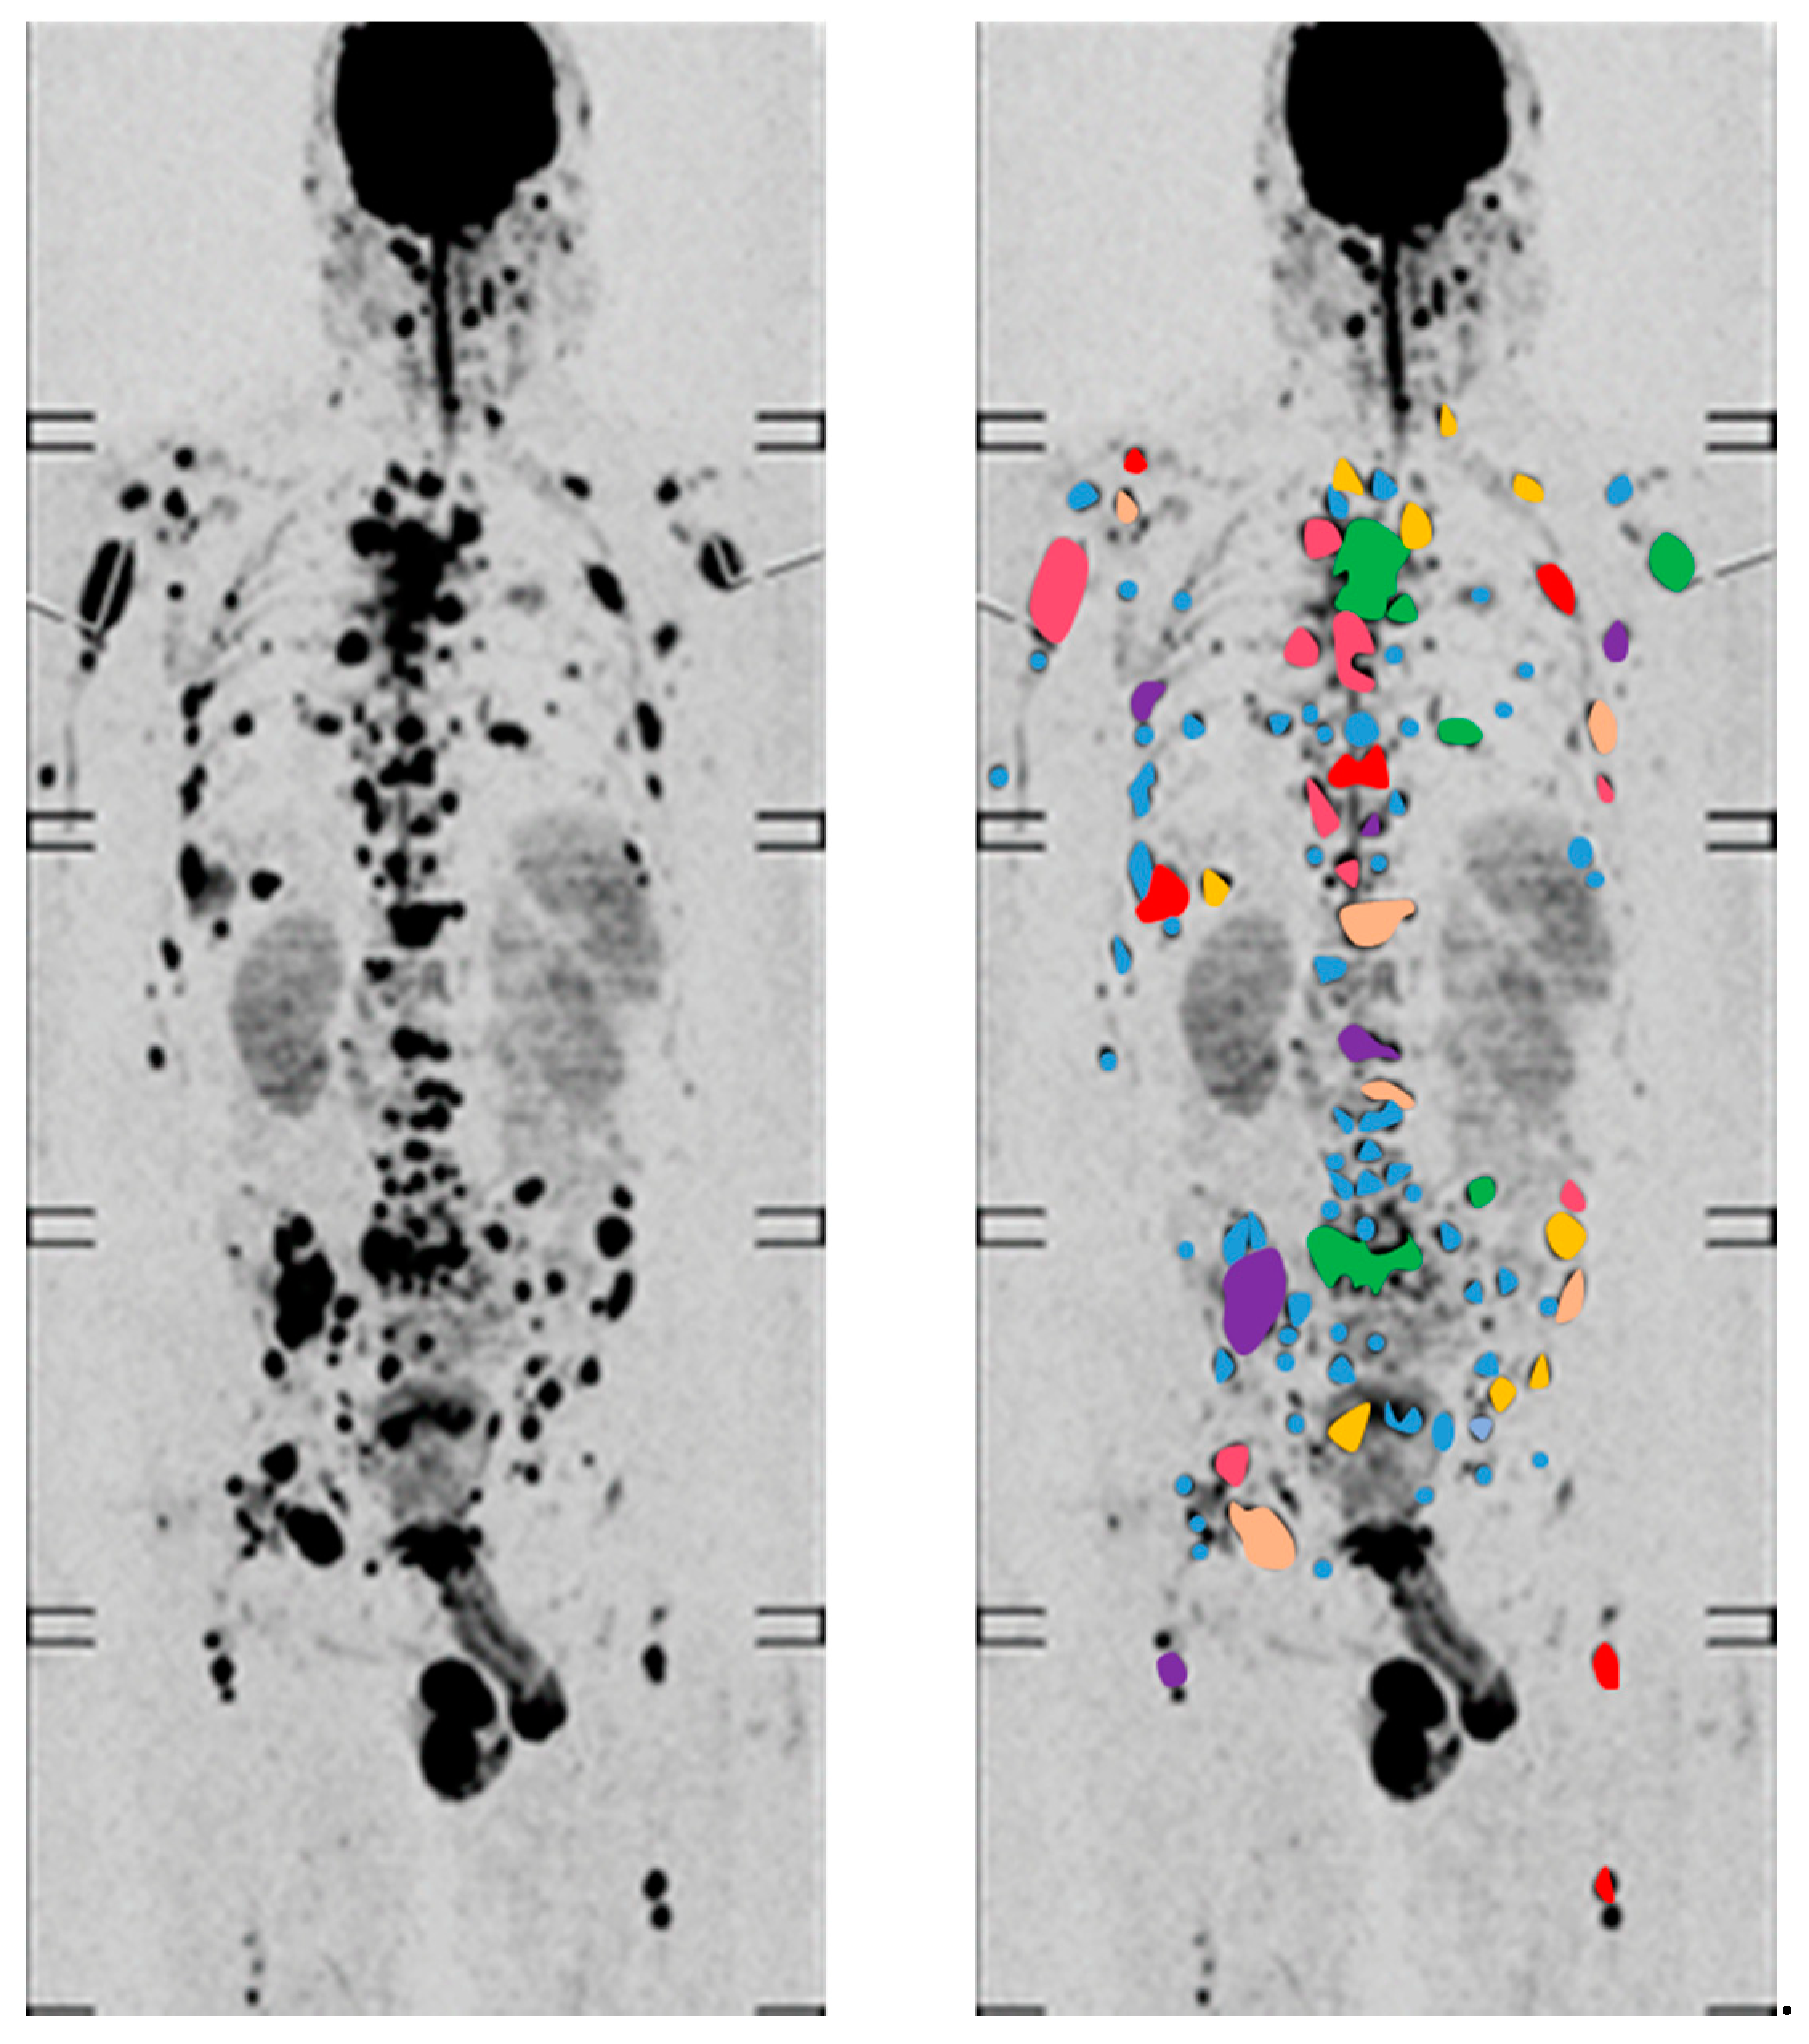

- Rasche, L.; Alapat, D.; Kumar, M.; Gershner, G.; McDonald, J.; Wardell, C.P.; Samant, R.; Van Hemert, R.; Epstein, J.; Williams, A.F.; et al. Combination of flow cytometry and functional imaging for monitoring of residual disease in myeloma. Leukemia 2018. [Google Scholar] [CrossRef]

- Rasche, L.; Chavan, S.S.; Stephens, O.W.; Patel, P.H.; Tytarenko, R.; Ashby, C.; Bauer, M.; Stein, C.; Deshpande, S.; Wardell, C.; et al. Spatial genomic heterogeneity in multiple myeloma revealed by multi-region sequencing. Nat. Commun. 2017, 8, 268. [Google Scholar] [CrossRef]